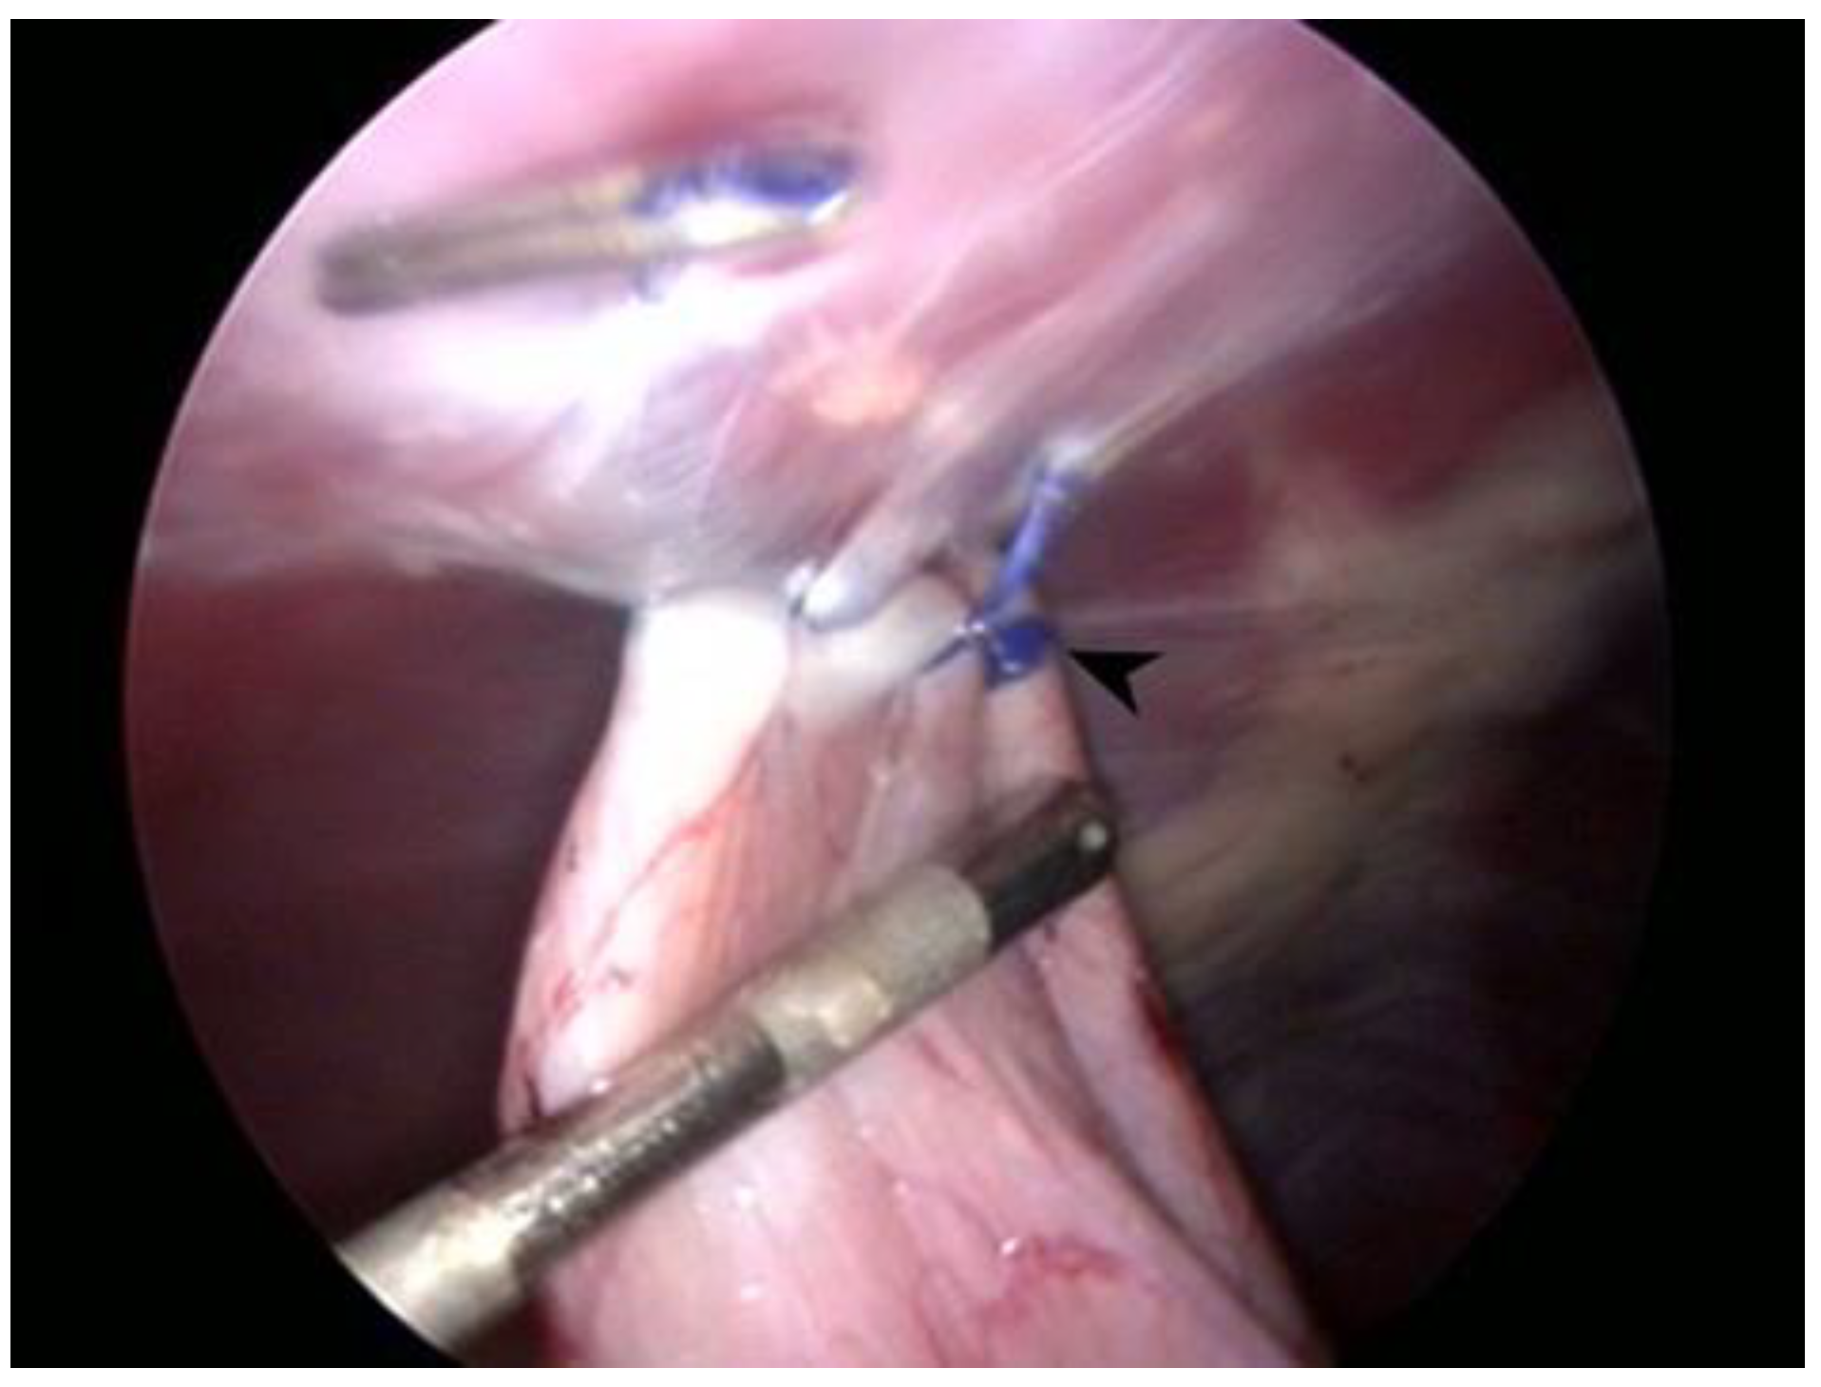

All dogs were prepared for aseptic surgery. The ventrolateral abdomen was clipped and scrubbed down as in a traditional laparotomy procedure. The surgeries were performed by two surgeons with more than 15 years of experience with laparoscopic procedures and over 3 years of experience with performing total laparoscopic prophylactic gastropexy procedures. Each dog was placed in dorsal recumbency. In all procedures, a three-port technique was used, as previously reported [23,24,25]. The first port (T1) was created via the open Hasson approach. Specifically, a 12 mm cannula (T1) (Trocar Hybrid, X-ONE, MediLine, S. Gregorio, Italy) 1 cm caudal to the umbilicus was placed in the right paramedian position to avoid overlap with the falciform ligament. Capnoperitoneum was established by a CO2 automatic insufflator at a pressure level of 10–12 mmHg. A 5 mm 0° telescope (HOPKINS II, KARL STORZ Endoscopy, Goleta, CA, USA) was inserted through T1. Via direct observation, the second (T2) and third ports (T3) were placed approximately 8–10 cm apart cranially and caudally to T1 using two 6 mm EndoTIPs (TERNAMIAN EndoTIP Cannula, KARL STORZ Endoscopy, Goleta, CA, USA) in the right paramedian position. Once all ports had been established, the insufflator pressure was reduced to 8 mmHg. A telescope was inserted in T2, and two laparoscopic needle holders (LOFT-LINE needle holder, Tontarra Medizintechnik GmbH, Wurmlingen, Germany) were introduced in T1 and T3. After abdominal exploration, a self-retaining knotless unidirectional barbed suture with a polydioxanone (PDO) button (0 Filbloc, 15 cm, PDO monofilament long term absorption, Assut Europe, Roma, Italy; HSRG 36 mm-1/2 tapper cutting, Assut Europe, Roma, Italy) (Figure 1) was held by a needle holder and brought into the abdomen through T1. The needle was then held intracorporeally with the other needle holder and positioned as previously described [22]. The first bite was taken on the seromuscular layer of the pyloric antrum, halfway between the lesser and greater curvatures, and the stomach was anchored at the abdominal wall in a right paracostal position, 2–3 cm caudal to the last rib. Before proceeding with the simple continuous suture pattern, it was necessary to apply tension to the suture line to prevent backward movement and to allow adequate contact between the stomach and the transversus abdominis muscle. Two to three more bites were performed 5–7 mm apart, and then a titanium endoclip (Endo Clip 5 mm, Medtronic, Minneapolis, MN, USA) was applied on the suture line to create a landmark for the short- and long-term follow-up examinations and the suture was cut intracorporeally (CLICKline Scissors, KARL STORZ Endoscopy, Goleta, CA, USA). Once the procedure was completed (Figure 2), the strength of the gastropexy line and the length of the suture were both evaluated with a 5 mm probe (Palpation Probe with cm marking, KARL STORZ Endoscopy, Goleta, CA, USA). After abdomen deflation, port site closure was performed in a standard manner using 0 or 2-0 polyglyconate to oppose the muscle layer and the subcutaneous layer, and skin closure was achieved using tissue adhesive (3M Vetbond, 3M Health Care, St. Paul, MN, USA). If other elective procedures (i.e., ovariectomy or castration) had to be performed, they were done after gastropexy. The total surgery time (from first skin incision to last port closure), gastropexy time (from the insertion of the instruments in the ports to suture completion), length of suture, number of bites, performance of other procedures, and presence of intraoperative complications were recorded.

Figure 2.

Laparoscopic image at the end of the gastropexy procedure while measuring the suture length. Note the button at the beginning of the suture (arrowhead) and the endoclip at the opposite end.